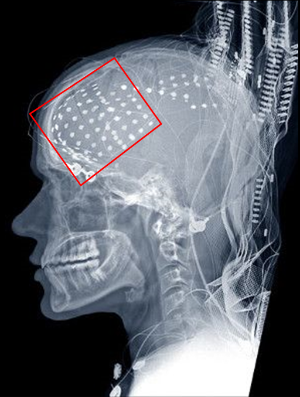

엑스레이 사진

인간의 뇌에서 언어를 담당하는 대표적인 부위가 '베르니케 영역'과 '브로카 영역'입니다. 베르니케 영역은 청각피질과 시각피질로부터 전달된 언어정보의 해석을 담당하고 있습니다. 그리고 브로카 영역은 언어 생성을 제어하고 말을 하는 기능을 담당하고 있습니다. 브로카 영역은 19세기 프랑스의 의사 '폴 피에르 브로카'에 의해 발견되었으며, 말을 하기 위하여 입술이나 혀 등을 움직이는 작용을 하기 때문에 운동성 언어 중추라고도 불리웠다고 합니다. 그런데 최근에는 100년 이상 믿어져온 브로카 영역의 작용에 대해 의구심을 갖게 될 수 있는 결과가 미국의 존스 홉킨스 대학의 연구자들에 의해 발견되었다고 합니다. 그들은 7명의 간질환자의 협력을 얻어 실험을 실시하였는데, 간질 치료 중인 뇌의 브로카 영역에 걸쳐서 시트 모양의 센서(전극)을 128개 배치하고, 피험자들이 말을 듣고, 말을 하는 과정에서 뇌의 활동을 측정했습니다. 이 실험은 본격적인 브로카 영역에 대한 연구는 아니었습니다만, 실험 결과에 의하면 실제로 말을 하는 동안 브로카 영역은 별다른 반응을 보이지 않았고, 운동과 관련된 뇌의 영역이 활동을 하고 있었다고 합니다. 하지만 그렇다고 해서 브로카 영역이 언어 중추가 아니라는 이야기는 아닙니다. 브로카 영역은 오히려 말을 하기 전에 활발한 활동을 하고 있었다고 합니다. 즉, 지금까지 생각된 것처럼 말을 하는 행동 그 자체에 영향을 주고 있었던 것이 아니라, 말을 하기 위해 필요한 정보를 뇌 안에서 정리하여, 대화를 할 수 있도록 지시하는 일종의 허브 역할을 하고 있었다는 것 입니다.